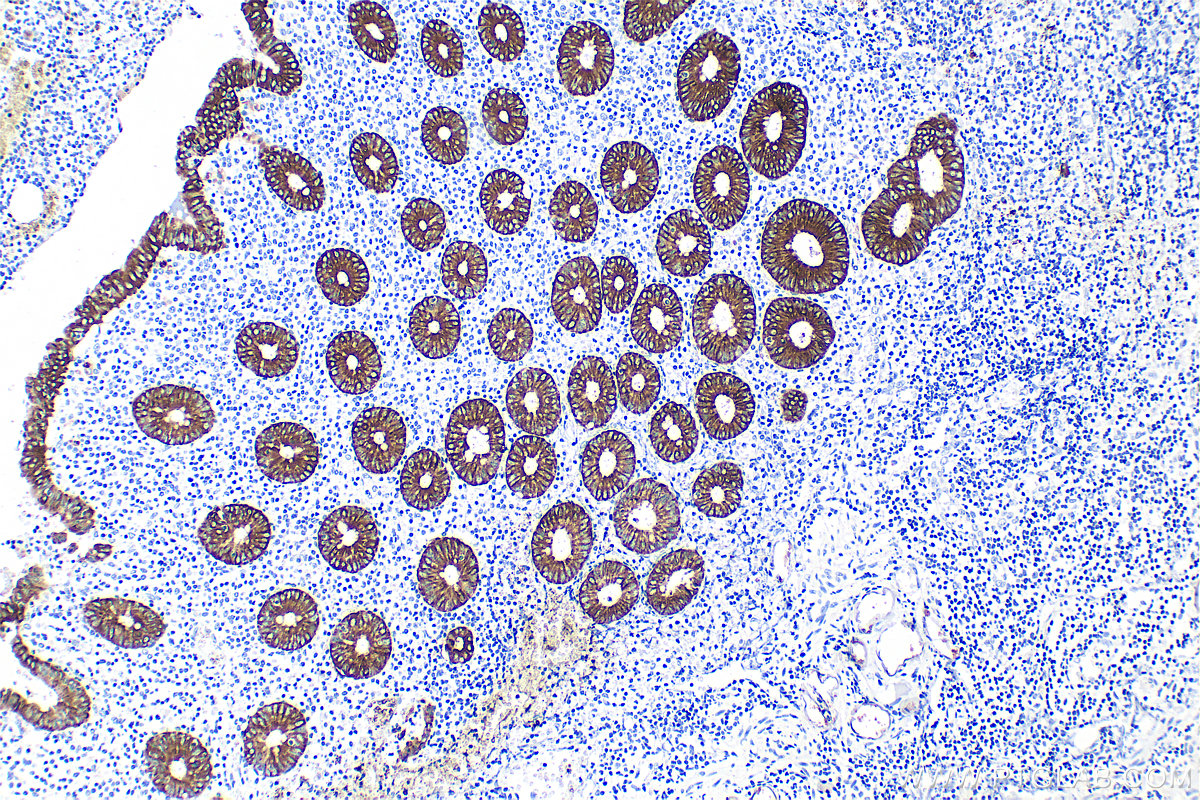

| Positive IHC detected in | human tonsillitis tissue, human appendicitis tissue, human bowen disease tissue, human breast cancer tissue, human colon tissue, human liver tissue, human renal cell carcinoma tissue Note: suggested antigen retrieval with TE buffer pH 9.0; (*) Alternatively, antigen retrieval may be performed with citrate buffer pH 6.0 |

Cytokeratin 8 (CK8) is a protein that belongs to the cytokeratin family, which is a group of structural proteins found in the intracytoplasmic cytoskeleton of epithelial cells. CK8 forms intermediate filaments within the cytoplasm of simple epithelial cells, typically as a dimer with cytokeratin 18 (CK18). These filaments provide a stabilizing framework that helps determine cell shape and enables cells to cope with mechanical stress. CK8/CK18 filaments also serve as a mesh of "paths" for signaling molecules, metabolites, and pathogens to travel within the cell in an organized manner. CK8 is expressed in various epithelial tissues and is particularly associated with glandular and simple epithelia. Its expression is also a significant marker in several types of cancer, including lung and esophageal cancer, where it can indicate tumor progression and poor prognosis.